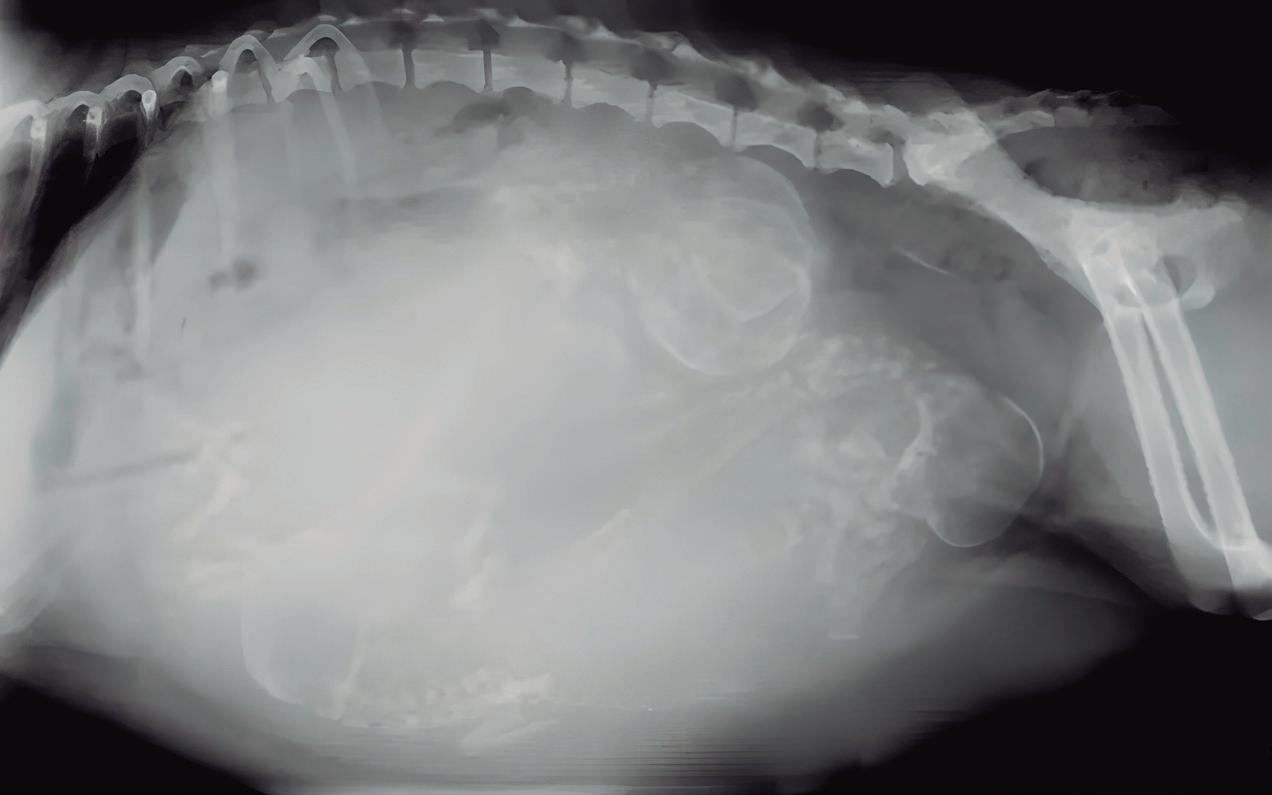

Causas del aborto espontáneo en perros

La llegada de nuevos miembros caninos a nuestro hogar es sin duda una buena noticia. Para ello, hay que asegurarse de que la madre tiene un embarazo lo más llevadero posible. Sin embargo, a menudo ocurren imprevistos que pueden desencadenar el aborto espontáneo en perros.

El aborto en perros: el cuándo es importante

El período de gestación de una perra –entre 63 y 67 días aproximadamente– es uno de los momentos más delicados para el animal. Durante ese tiempo, se da un complejo equilibrio a nivel físico, hormonal y nutricional que hace que los embriones consigan desarrollarse y crecer.

Sin embargo, durante todo ese tiempo, desafortunadamente, algo puede torcerse. Y el momento en que esto ocurra puede influir en mayor medida en nuestra mascota y su posible

descendencia. Por lo general, los abortos o interrupciones del embarazo que ocurren antes de la quinta semana suelen tener relación con una posible infertilidad del animal.

En estos casos, los embriones no desarrollados pasan a ser reabsorbidos. Esto no tiene consecuencias negativas para la madre, y es que llega incluso a pasar desapercibido. No obstante, el aborto espontáneo en perros a partir de la quinta semana de gestación pasa factura, ya que conlleva muchos dolores y es más difícil de sobrellevar a todos los niveles.

¿Cuáles son las causas más comunes de aborto?

Como ya hemos comentado, la gestación en perros está sujeta a una serie de factores que mantienen un equilibrio. Es por esto que el desequilibrio en algunos de estos factores –sobre todo en la última fase del embarazo– puede

12 Revista Mascotas Abril 2024 Informe Técnico Veterinario

llevar al resultado del aborto espontáneo. Uno de estos factores tiene que ver con las hormonas, y es que cualquier desajuste de este sistema –por ejemplo, en la progesterona– provoca alteraciones prácticamente irreversibles.

Algunos medicamentos también pueden influir negativamente en el desarrollo de los cachorros, por lo que es importante que haya una supervisión estricta por parte del veterinario, en el caso de que fuera necesario administrar fármacos a nuestra mascota.

El aborto espontáneo en perros también puede tener una causa microbiana.

Algunas bacterias –de los géneros Brucella o Listeria, entre otros– son las responsables de causar trastornos irreversibles que derivan en la interrupción del embarazo. Otros microorganismos pueden aparecer en lugares tan comunes como la comida o el agua, por lo que la vigilancia sobre la dieta del animal se hace imprescindible.

Por último, existen una serie de factores ‘internos’ que pueden influir negativamente en la gestación. Quizá el más relevante de ellos es la edad, ya que los embarazos empiezan a ser un factor de riesgo a medida que nuestra mascota envejece.

Síntomas del aborto espontáneo en perros

Detectar que algo va mal en el embarazo de nuestra mascota no es tarea fácil. La razón principal es que los síntomas que pueden presentarse son bastante inespecíficos, como por ejemplo:

• Dolor abdominal.

• Fiebre.

• Vómitos y diarreas.

• Pérdida de apetito y apatía.

Otros síntomas como el sangrado abundante o la secreción vaginal anor-

mal son más indicativos y, si los detectamos, debemos acudir rápidamente al veterinario. Una vez realizado el diagnóstico, nos podrá informar sobre los pasos que haya que seguir, además de señalarnos la posible causa. Si por desgracia el aborto espontáneo tiene lugar, nosotros como dueños debemos centrar toda nuestra atención y nuestro cariño hacia la perra, ya que probablemente se muestre deprimida y cansada. Si todo va bien, con nuestra ayuda poco a poco nuestra mascota volverá a ser la de antes.